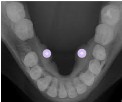

Oclusal torus

Marina Delgado